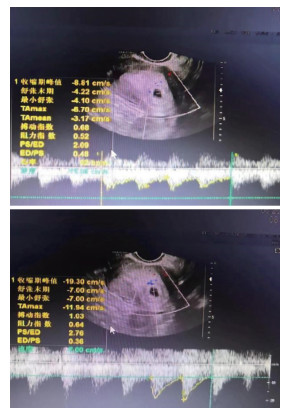

Prognostic effect of ultrasonic arterial flow parameters combined with serum ACA and AMH detection on fetal saving outcome of threatened abortion

GUAN Yanli, ZHANG Li, PEI Lijuan, ZHANG Mei

2025, 23(10): 1748-1752. doi: 10.16766/j.cnki.issn.1674-4152.004220

378 5

Abstract:

Objective  Threatened abortion (TA) may still lead to abortive failure after treatment. In this study, ultrasound arterial flow parameters in combination with serum anti-cardiolipin antibody (ACA) and anti-Mullerian hormone (AMH) were detected to explore the predictive effect of these indicators on abortive outcome, with a view to improving the success rate of TA.  Methods  The current study is based on a total of 135 TA patients admitted to Sanmenxia Hospital and Nanyang Central Hospital of the Yellow River from May 2021 to May 2023. According to the outcome of fetal protection, they were divided into a successful group (n=83) and a failed group (n=52). All patients had their ultrasonic arterial blood flow parameters and serum hormone levels checked. The influencing factors of fetal survival outcome were analyzed by means of a logistic regression model. The receiver operating characteristic (ROC) curve was utilized to analyze the predictive value of ultrasonic arterial flow parameters, serum ACA and AMH in the outcome of fetal protection.  Results  In contrast with the abortive group, the end-diastolic flow rate (D) and AMH levels in the abortive group were decreased, while the peak systolic flow rate (S)/D, pulse index (PI), resistance index (RI), ACA level and spontaneous abortion history, and the proportion of vaginal bleeding ≥50 mL were increased in the abortive group (P < 0.05). Logistic regression analysis showed that vaginal bleeding of ≥50 mL, elevated high levels of S/D, PI, RI and ACA were independent risk factors for fetal failure of TA (P < 0.05, OR>1), and high levels of AMH were protective factors (P < 0.05, OR < 1). The results of the ROC analysis demonstrated that the AUC of S/D, PI, RI, ACA and AMH were 0.724, 0.676, 0.752, 0.755, 0.692 and 0.880, respectively, and the combined prediction efficiency of the five factors was found to be superior to that of each individual test.  Conclusion  Abnormal ultrasonic arterial flow parameters in TA patients, among which high levels of S/D, PI, RI and ACA are risk factors for the failure of TA, and high levels of AMH are protective risk factors. The five combined tests have a high level of predictive capacity for the outcome of TA.